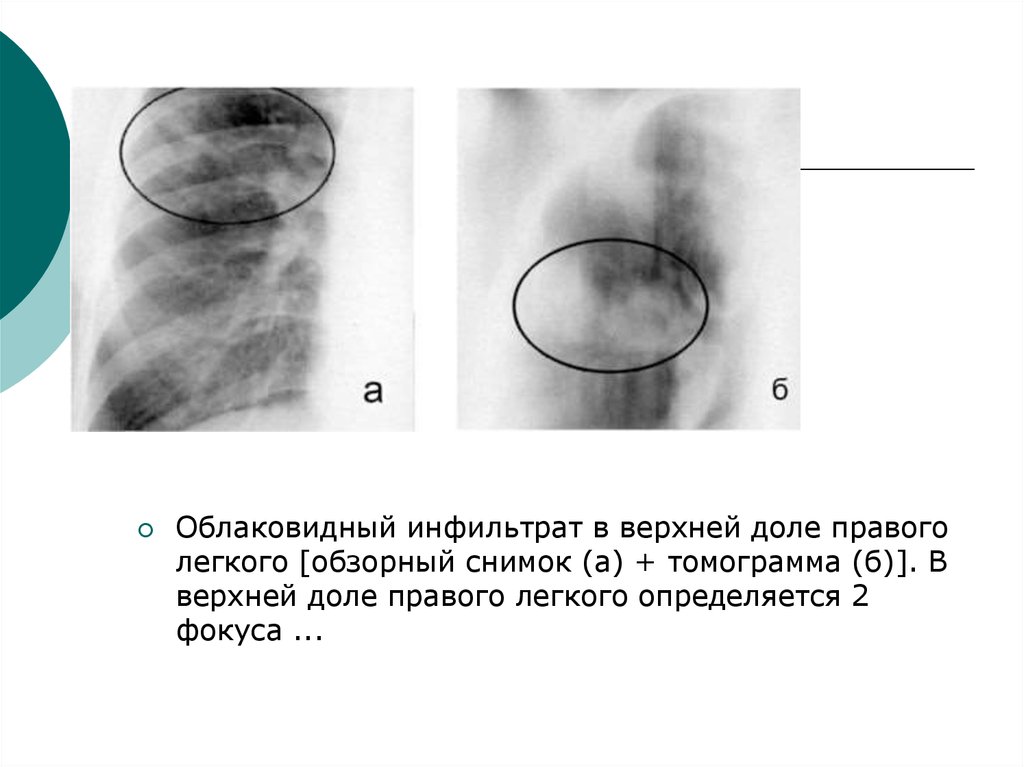

Симптомы и лечение инфильтративного туберкулеза легких

Раздел: Снимки-откровения